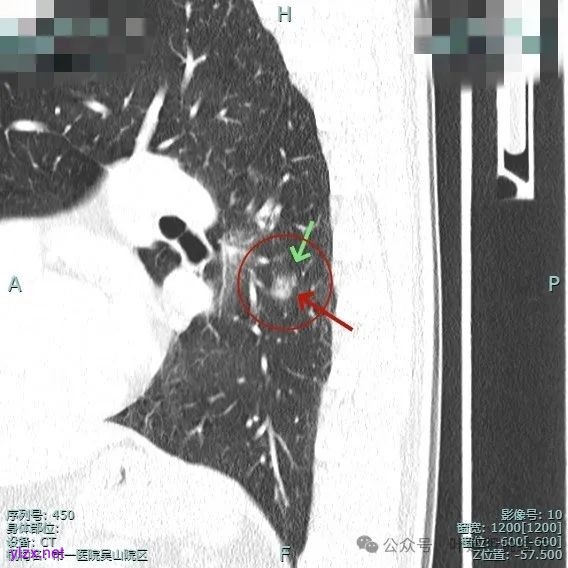

主病灶有血管进展与异常增粗,灶内有实性成分,中间有小空泡征。

进入病灶内的血管壁毛糙不平,有异常增粗。

血管进入且异常增粗,其余部分密度为磨玻璃及少许点状偏高成分。

轮廓清,血管明显。

表面有浅分叶征,整体轮廓清。

灶内小空泡征,边缘略显毛糙,整体轮廓较清。

血管进入扭曲,毛刺明显,整体轮廓清,灶内小空泡征。

主病灶血管进入,灶内空泡,表面浅分叶,整体轮廓较清。